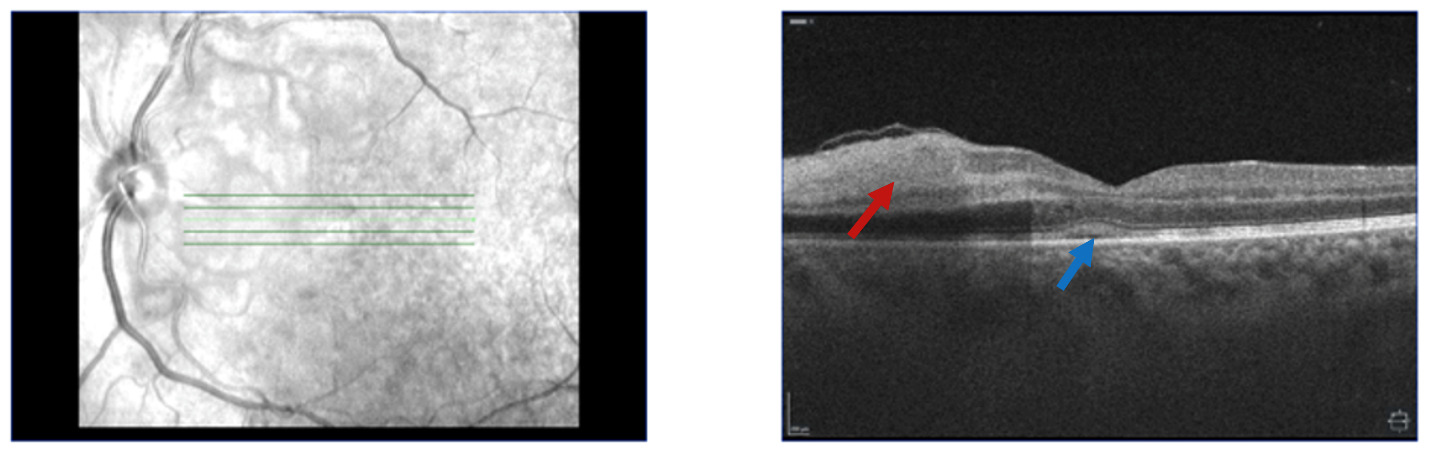

On outpatient follow up one week later, the patient was assessed by a retina specialist where she reported improvement of her visual symptoms. Her visual acuity was 20/60 on the right and 20/100 on the left. Slit lamp exam was normal OU. Fundoscopic exam revealed bilateral peripapillary and posterior pole retinal whitening consistent with Purtscher flecken along with scant inferior intraretinal hemorrhages. Ocular coherence tomography (OCT) showed inner retinal hyperreflectivity / thickening in the nasal macula and focal scant subfoveal subretinal fluid, with the left eye being more affected than the right (Figures 1 and 2). These OCT findings were consistent with acute microvascular ischemia. Decision for conservative management was made and no systemic steroids were administered, given the limited evidence of improved visual outcomes with steroid treatment, as well as the potential ocular side effects of steroid treatment including cataracts, glaucoma and ocular hypertension.8

The patient was subsequently followed up every 2-3 months with repeat dilated exams and OCT. She reported gradual improvement of her visual symptoms. Fundoscopic exam at 5 and 8 months after discharge revealed complete resolution of all the retinal spots, while repeat OCT demonstrated inner retinal thickening consistent with chronic retinal injury. The patient was advised that she could expect further visual improvement over the next several months, but there would likely be some permanent visual deficit.